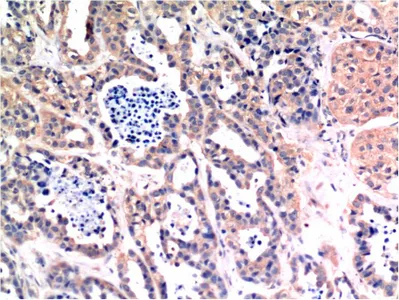

CDX2(14H6)Mouse Monoclonal Antibody

Cat: AMM08595

Size1:50μL Price1:$118

Size2:100μL Price2:$220

Size3:200μL Price3:$380

Application:WB,IF-P,IF-F,ICC/IF,IHC-P

Reactivity:Human,Mouse,Rat

Conjugate:Unconjugated

Optional conjugates: Biotin, FITC (free of charge). See other 26 conjugates.

Gene Name:CDX2